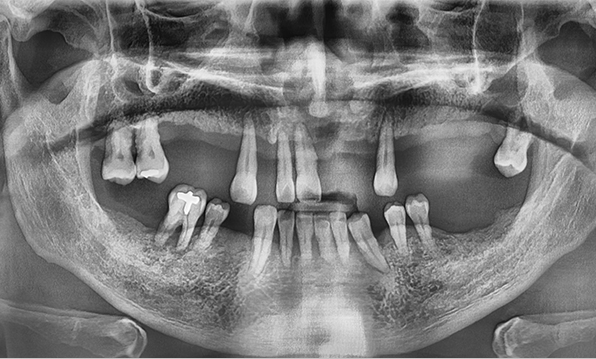

Unlike single or dual implant cases, full-mouth implant restoration is a high-complexity surgical procedure that rehabilitates the entire oral cavity. It is a treatment that demands extensive clinical experience and specialized implant expertise.

In full-mouth implant cases, implants are placed only where needed, and the remaining gaps are restored using a bridge (pontic) method — minimizing the total number of implants while achieving masticatory force comparable to natural teeth, helping to reduce the financial burden.

Full-mouth implant restoration is categorized into full placement or minimal placement approaches.